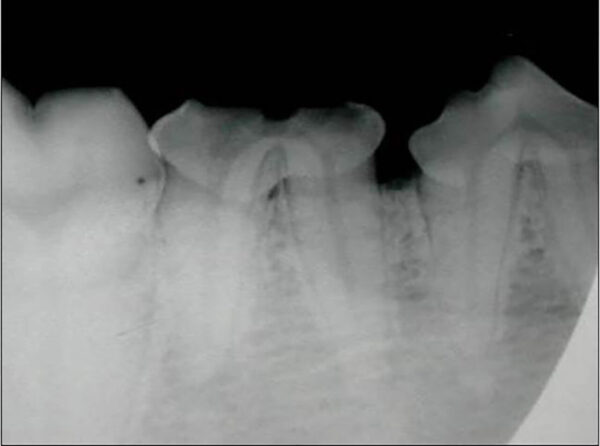

Uno de los aspectos importantes de la radiología es reconocer las estructuras del diente para detectar sus posibles alteraciones. En la imagen 1 se muestra una radiografía intraoral de un primer molar mandibular derecho (409) sano que nos permite ilustrar e identificar su aspecto radiológico. Así, el esmalte, la dentina y el hueso alveolar son radiopacas y la cámara y canal pulpar, así como el espacio del ligamento periodontal, son radiolúcidas.

Dentro de las estructuras anatómicas también podemos evaluar la maduración del canal pulpar, ya que este disminuye gradualmente con la edad por la formación continua de dentina secundaria. Así, por ejemplo, en el gato a los 6 meses su tamaño es de 0,56 mm, a los 12 meses de 0,27 mm, a los 32 meses de 0,18 mm y a los 5 años de 0,15 mm (Kyoungsun, 2014). Esto nos permite aproximarnos a la edad del paciente, como hemos mencionado anteriormente.